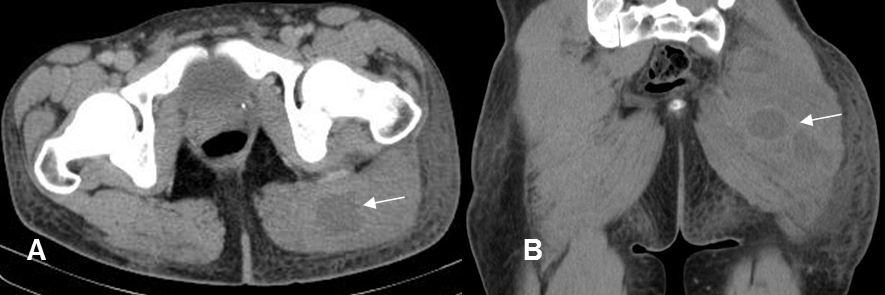

Fig 17. Absceso de tejidos blandos.

A: TAC axial y B: TAC coronal. Igual paciente anterior. Días después se detectan colecciones dentro del músculo, cuyos bordes captan el contraste, por la formación de absceso. Estos hallazgos ya se insinuaban en el estudio inicial.